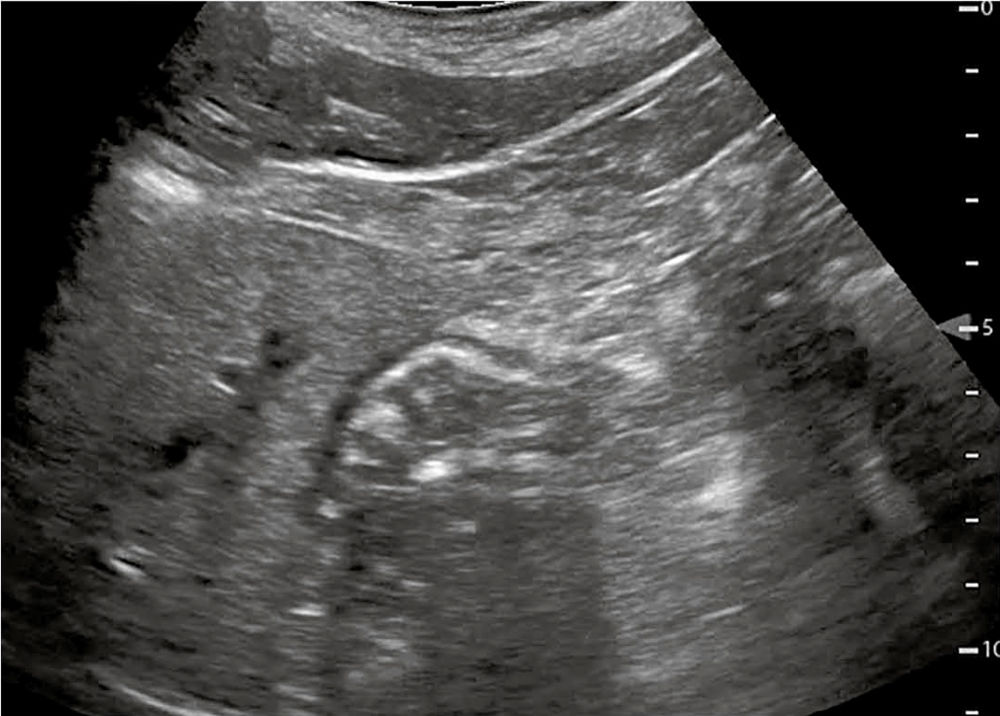

Regionalanästhesieverfahren sind besonders in der perioperativen Medizin gut etabliert, wobei wie beschrieben insbesondere ultraschallgestützte periphere Verfahren aufgrund ihrer hohen Sicherheit und Effektivität zunehmend Verwendung finden [33]. In Deutschland stellen Regionalanästhesieverfahren in der Notfallmedizin bislang keinen Leitlinienstandard dar, könnten jedoch bald in die S2k-Leitlinie zur Katastrophenmedizin aufgenommen werden, da bereits auf europäischer Ebene entsprechende Verfahren in Leitlinien enthalten sind [34] und in bestimmten Situationen routinemäßig eingesetzt werden. Beispielsweise kommt der Fascia-iliaca-Block (Abbildungen 11 und 12) bei hüftgelenksnahen Frakturen in 60 Prozent der Einrichtungen des National Health Service (NHS) zum Einsatz. Gleiches gilt für die USA, wo 2022 sowohl Verfahrensrichtlinien zu standardisierten Abläufen [35] als auch evidenzbasierte Empfehlungen zur Anwendung regionalanästhesiologischer Techniken in der pädiatrischen Notfallmedizin veröffentlicht wurden [36]. Fichtner und Kollegen haben in einer Review-Arbeit herausgestellt, dass Regionalverfahren den gesamten Behandlungsprozess deutlich effizienter gestalten, wenn sie bereits in der präklinischen Phase angewendet werden [37]. Erst die flächendeckende Verfügbarkeit von tragbaren Handheld-Ultraschallgeräten im Rettungs-/Notarztdienst macht die Regionalanästhesie der präklinischen Notfallmedizin mit der erforderlichen Sicherheit zugänglich [38].

Abbildung 12: Sonoanatomie Fascia-iliaca-Blockade